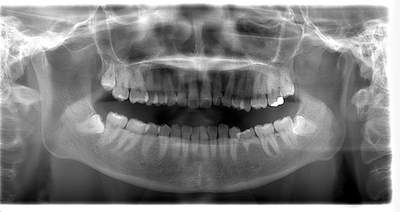

左下親知らずがたまに痛み、

できれば痛くなく抜きたい症例

- 抜歯前写真(レントゲン)

| 年齢 | 20代・女性 |

|---|---|

| 主訴 | 左下親知らずがたまに痛み、できれば痛くなく抜きたい |

| 親知らずの生え方 | 完全に埋まっている、横向きに生えている |

| 抜歯時間 | 50分 |

| 費用 | 約8,000円(保険診療、CT代含む) |

| 抜歯内容 | 左下親知らずが横向きになって半分埋まっている状態だったため、麻酔を行い、親知らずの奥の歯ぐきに切開をいれ、歯が囲んでいる骨を削り、歯の頭の部分を削って出し、その後根の部分に器具をかけて抜歯しました。 親知らずが一部神経に近い部分があったため、術後に麻痺が出る可能性がありました。このケースでは事前にCTを撮影し、歯の位置、根の方向、神経との距離を確認していたため、幸い麻痺が出ることはありませんでした。 術後1週間経過して糸取りをして治療は終了となりました。抜歯後3日間は腫れと痛みで大変だったが、糸取りをする頃には痛みも腫れも無くなったと患者さまも喜んでおられました。 |